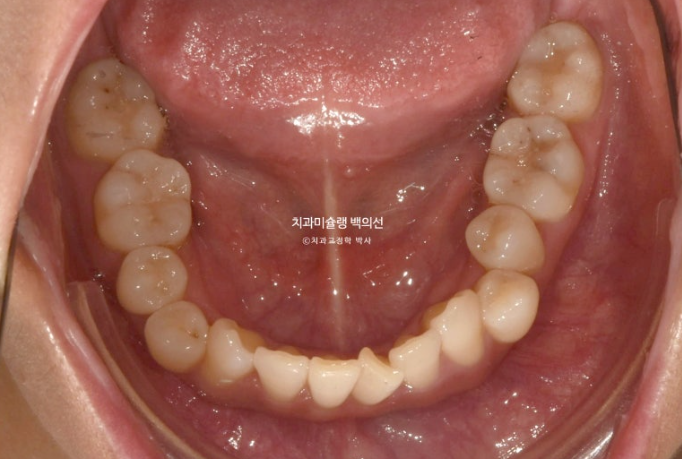

24년 8월부터 25년 4월까지, 31개 장치를 모두 낀 후 모습입니다.

31개 장치를 끼는 동안 중간 내원 횟수는 3회

환자분 협조도가 좋아서 나중엔 3달 간격으로 진료를 보았습니다.

중심선이 맞아지고 과개교합도 해결되었고 아래앞니 치축 기울어짐이 보입니다.

덧니가 배열되며 반대교합도 해소가 되었습니다.

아래 앞니 배열이 약간 아쉽습니다.

이 부분들을 고치기 위해서 재제작에 들어갔습니다.

25년 5월부터 8월까지, 4달간 16개 추가장치를 모두 낀 후 치료를 마무리 했습니다.

철사 유지장치까지 붙은 모습입니다.

현재는 가철식 유지장치로 비베라를 제작중에 있습니다.

1년간의 치료기간 동안 치근흡수는 없고 뿌리 평행도는 좋습니다